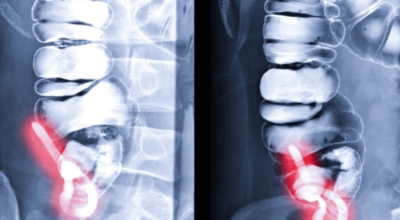

맹장염은 외과의사가 수술하는 복통 중 가장 흔한 질환이지요. 임상양상은 비천공성, 천공된 국소 복막염, 진행된 범발성 복막염 등으로 나타납니다. 대개 치료하지 않으면 충수돌기의 염증은 천공으로 진행되어 복막염이 돼요.

급성 충수염은 10~20대의 젊은 연령층에서 호발하고, 20대 초반에 가장 흔해요. 10세 이전이나 50세 이후의 맹장염 환자는 전체의 10%정도이지요. 맹장염은 의학용어로는 충수돌기염 및 충수염이라고 해요. 맹장은 대장의 시작하는 부분으로 충수돌기라는 창자가 붙어있는 곳이라서 충수돌기염을 맹장염이라고 불러요.

충수돌기가 위치하는 오른쪽 아랫배에 통증이 발생되는 증상이 일반적이지요. 아랫배에 통증이 느껴지는 부위를 누르면 통증이 더 극심해 지는데요. 매우 드물게 충수가 왼쪽에 있는 사람도 있다고 해요. 사람마다 충수돌기의 위치가 조금씩 다르므로 우측 옆구리에 통증이 일어날 수 있으며 변을 보고 싶은 증상이나 불편감이 발생하기도 해요.